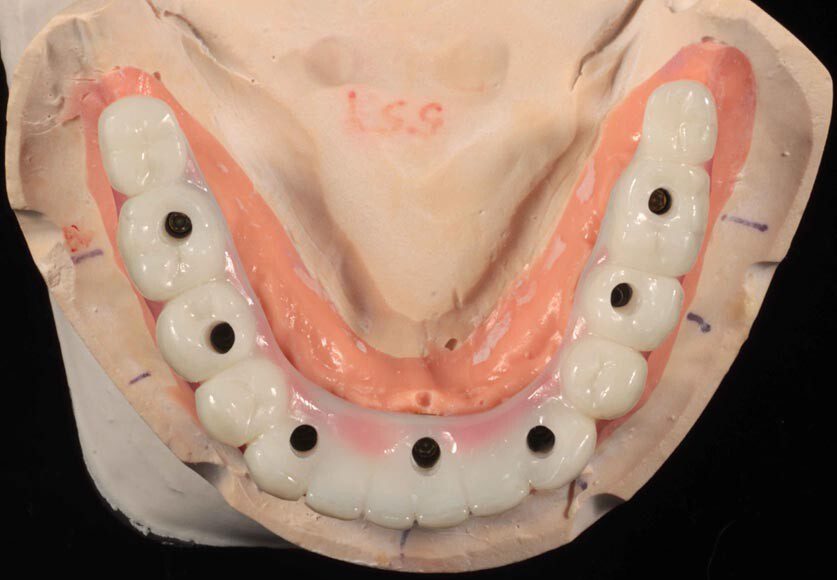

Three months post-surgery in the upper, the patient is ready to start the lower. Back, existing implants placed 9 months earlier when we tried to save teeth.